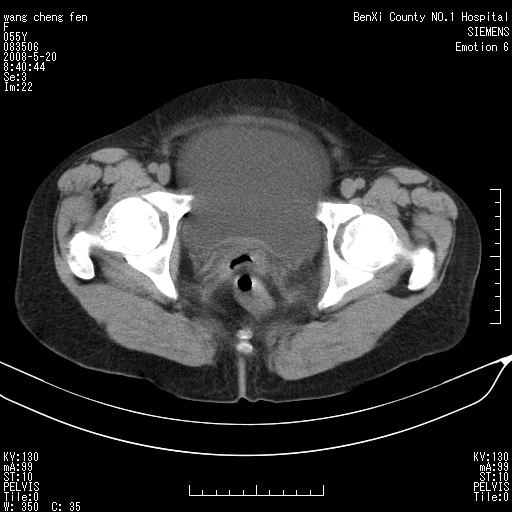

女、绝经后阴道流血3个月

宫颈略萎缩、宫颈前唇及阴道前臂可初级结节。

宫颈好像也有问题吧,大家在仔细看看,另外彩超回报为卵巢占位。建议ct。

支持浆膜下子宫肌瘤.之前由于网络原因未看全图片,现在重看,宫颈见一类圆形低密度影,增强轻度强化,低于肌层强化,宫腔扩大,考虑宫颈癌伴宫腔积液可能性大.

1,宫颈部占位,宫颈癌?2,左侧附件区囊实性占位,界较清,实质部分强化明显。考虑浆膜下或阔韧带肌瘤囊变可能大。囊腺类肿瘤不除外。